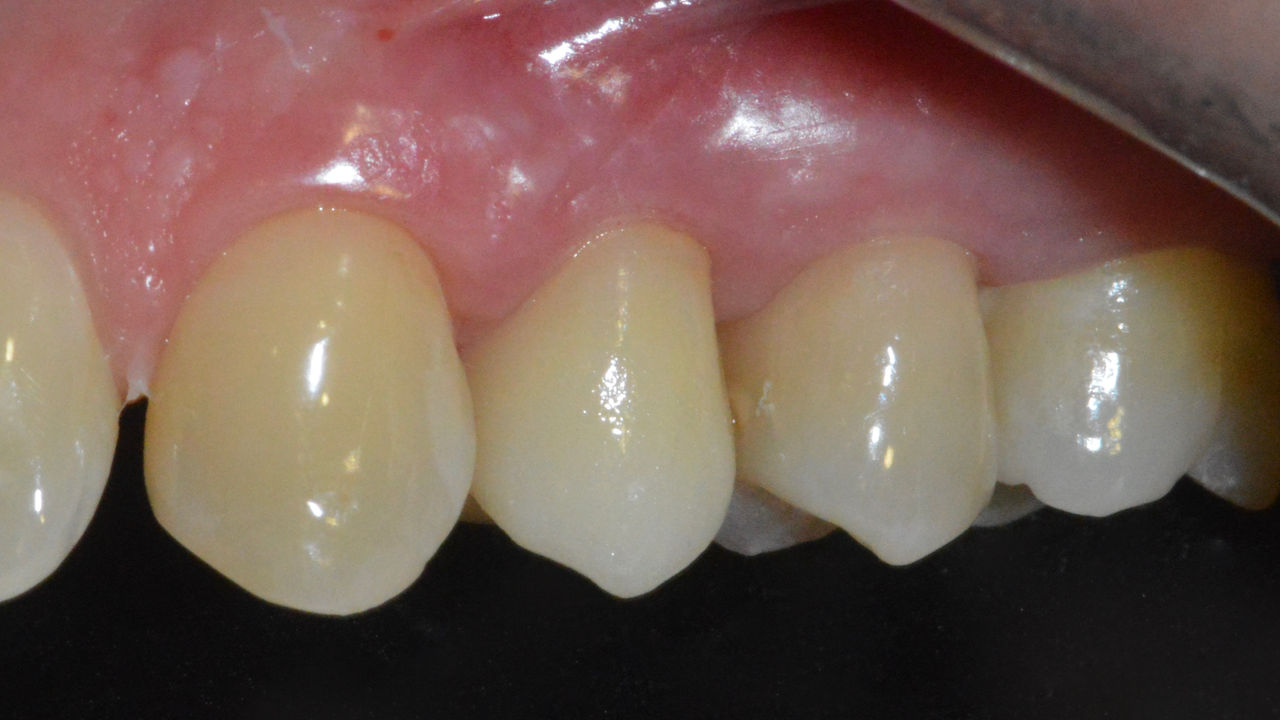

Before: Inadequate fillings on teeth 12-22, an uneven gingival line on 12 and 11 and incisal edges severely eroded.

After: Four highly esthetic and individualized lithium disilicate ceramic crowns.